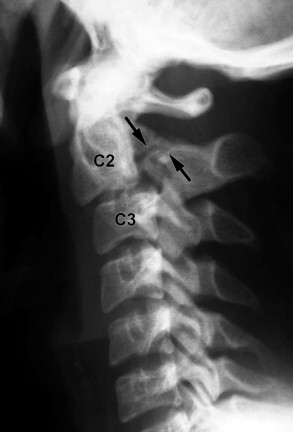

HANGMAN

- Fracture-dislocation of atlas and axis, specifically of pars interarticularis of C2 and disruption of C2–3 junction; separation occurs between second and third vertebral bodies from anterior to posterior side

- Results from extreme hyperextension during abrupt deceleration; most common cause is the forehead striking the windshield of a car during a collision;